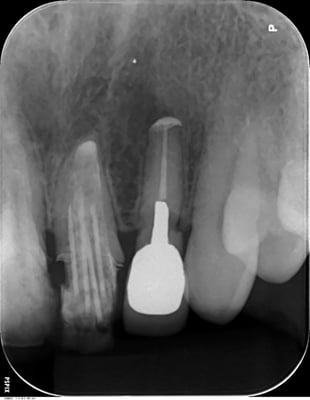

歯根端切除術 Apicopectomy

上顎右側側切歯 root endo sealing

coming soon!

右上側切歯

右上犬歯